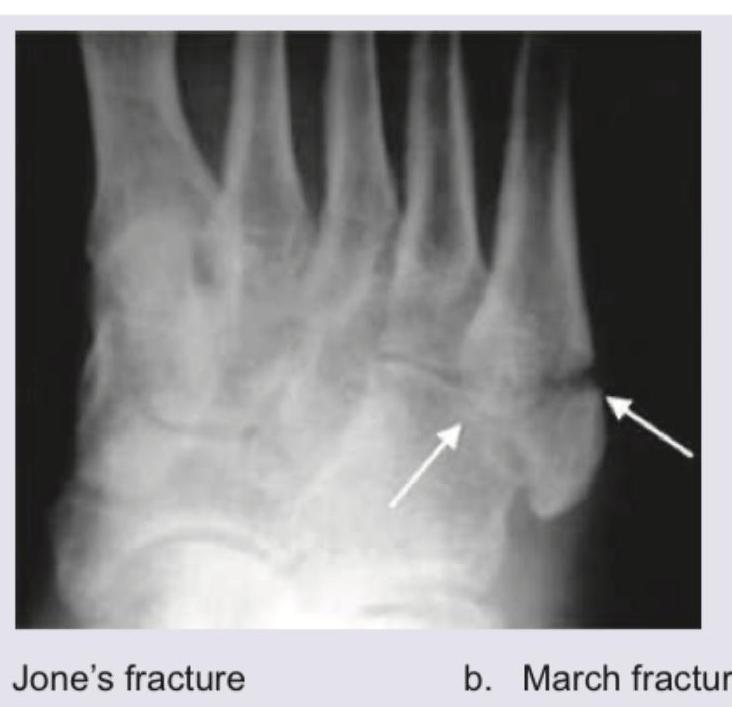

Comment on the diagnosis:

Explanation: ***Jones fracture*** - The image indicates a fracture located at the **proximal metaphyseal-diaphyseal junction of the fifth metatarsal**, which is characteristic of a **Jones fracture**. - This fracture involves the **base of the fifth metatarsal** and is often associated with a higher risk of nonunion due to limited blood supply. *March fracture* - A **March fracture** is a type of stress fracture, typically affecting the **shaft of the second, third, or fourth metatarsals**, often seen in military recruits or those who engage in prolonged walking or running. - It results from repetitive stress rather than an acute injury, and its location is distinct from the proximal fifth metatarsal. *Shepherd's fracture* - A **Shepherd's fracture** refers to an avulsion fracture of the **posterolateral tubercle of the talus**, also known as an os trigonum fracture. - This fracture is located in the ankle region, distinct from the metatarsals. *Cotton's fracture* - A **Cotton's fracture** is a trimalleolar fracture of the ankle, involving the **medial malleolus**, **lateral malleolus**, and the **posterior malleolus** of the tibia. - This is a complex ankle injury, entirely unrelated to fractures of the metatarsals.